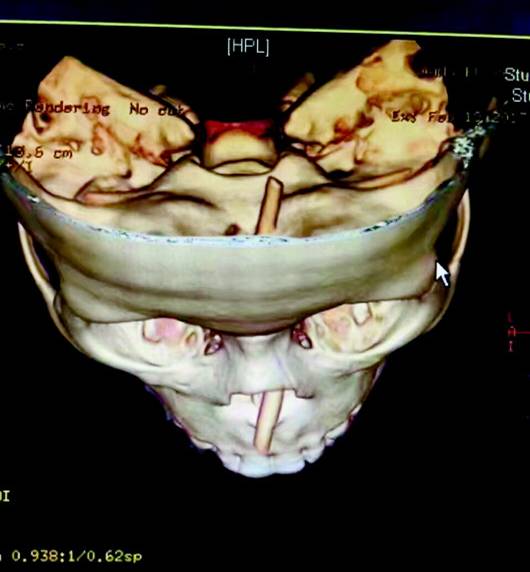

康康鼻孔內(nèi)筷子的三維重建圖像。(醫(yī)院供圖)

檢查結(jié)果讓姜彥主任大吃一驚。“左側(cè)的筷子有5厘米,從左鼻孔穿入后向左上傾斜,刺破眼眶、眶下肌,幸運(yùn)的是距離眼球僅有2到3毫米,并沒有觸碰到視神經(jīng),否則孩子左眼就廢了。右側(cè)的筷子有5.5厘米,從右鼻孔穿入后向左上傾斜,穿破了鼻中隔頂端,到達(dá)了顱底并刺破顱底骨質(zhì),穿入顱腦內(nèi)達(dá)1.48厘米,距離顱內(nèi)血管僅有一到兩毫米的距離。”姜彥告訴記者。